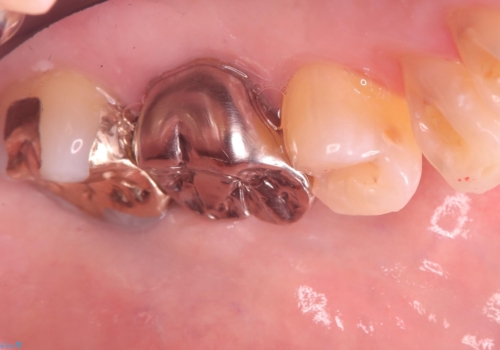

- 主訴:フロスを通したら、詰め物が取れた。適合の良いものを入れたい。

保険適用のメタルインレーが脱離しており、適合重視・咬合力が強いことからゴールドインレーでのやり替えとなりました。

フロスを通しインレーが脱離したことから、インレーと歯質との境に段差(適合不良)があった可能性があり、適合の良さや咬合力による補綴物の破折リスクを考慮し、ゴールドインレーでのやり替えとなりました。